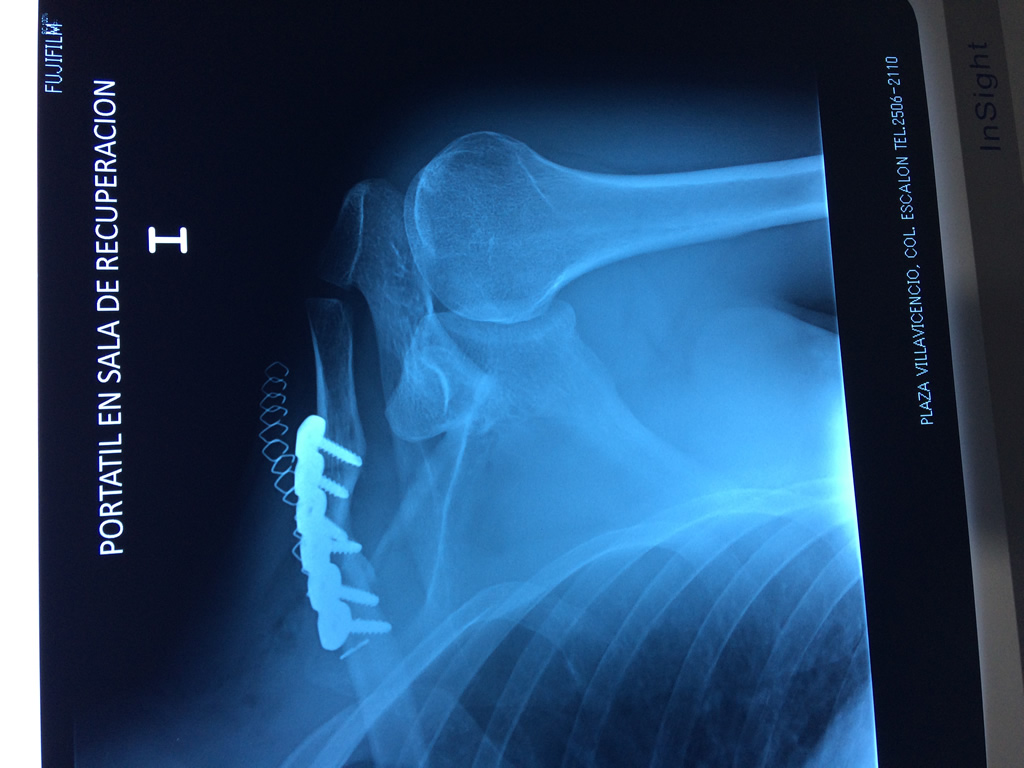

Húmero - Clavícula